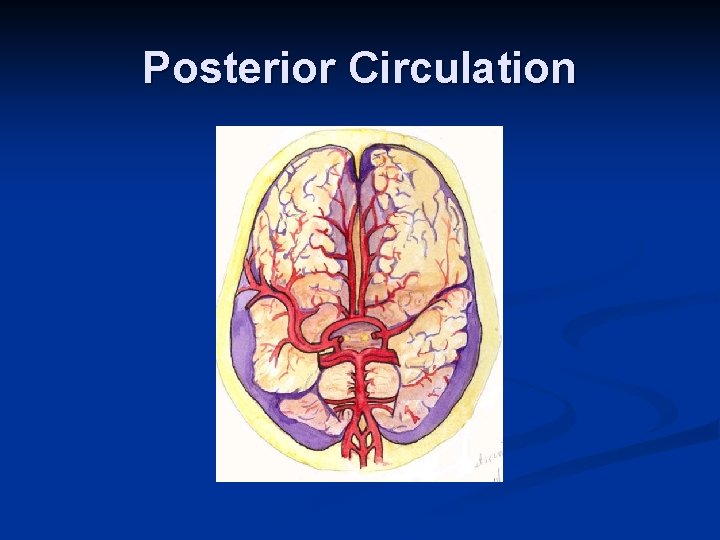

Vertebral Artery n Subclavian Steal n When a stenosis or occlusion of a the proximal subclavian or innominate and the effected side “steals” blood from retrograde vertebral artery flow

Vertebral Artery

Distinguishing characteristics of the vertebral artery: n First branch off subclavian n Enters foraminal canal at C 6 n Asymmetrical size: left > right n Low resistance flow

Posterior Circulation